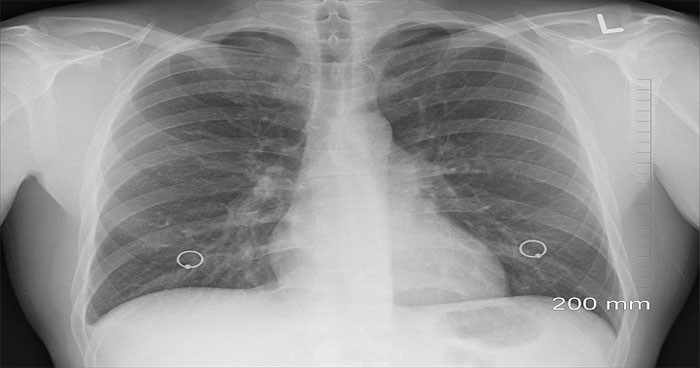

Ung thư trung biểu mô được xác định là do hít phải các hạt amiang, nơi bị ảnh hưởng nhiều nhất là ở niêm mạc phổi hoặc bụng. Hiện tại, có rất ít khả năng sống sót khi nhiễm amiang, chỉ có 7% số người sống sót trên 5 năm sau khi chẩn đoán bị nhiễm amiang, thông thường thời gian sống sót trung bình chỉ khoảng từ 12 đến 18 tháng.

Một nghiên cứu mới do Chương trình nghiên cứu ung thư trung biểu mô do trường Đại học Leicester thực hiện hiện đã tiết lộ, sử dụng phân tích AI để nghiên cứu trình tự DNA của các khối u trung biểu mô qua đó phát hiện rằng các tế bào ung thư này phát triển theo hướng tương tự hoặc lặp lại giữa các tế bào. Dựa trên cách thức này có thể dự đoán mức độ tích cực và liệu pháp điều trị phù hợp với căn bệnh ung thư không thể chữa khỏi này.

Giáo sư Dean Fennell, Chủ tịch Khoa Ung thư Y tế Lồng ngực tại trường Đại học Leicester đồng thời là Giám đốc Chương trình Nghiên cứu Ung thư Trung biểu mô Leicester cho biết: Từ lâu, người ta đã phát hiện rằng amiang là nguyên nhân gây ra ung thư trung biểu mô, tuy nhiên điều này xảy ra như thế nào vẫn còn là một bí ẩn. Việc sử dụng AI để xem xét các 'dữ liệu lớn' về bộ gen, công trình này sẽ cho chúng ta thấy được các khối u trung biểu mô đột biến có trật tự trong quá trình phát triển. Nhờ vậy mà có thể dự đoán được bệnh nhân có thể sống sót trong bao lâu để đề ra các điều trị thích hợp nhất - điều mà Leicester hướng tới thông qua các sáng kiến thử nghiệm lâm sàng.

Mặc dù việc sử dụng amiang hiện đã bị cấm cũng như hàng loạt các quy định nghiêm ngặt về việc sử dụng chất này - mỗi năm có khoảng 25 người được chẩn đoán mắc bệnh u trung biểu mô ở Leicestershire và 190 người được chẩn đoán ở East Midlands. Các trường hợp ung thư trung biểu mô ở Anh đã tăng 61% kể từ đầu những năm 1990. Cho đến gần đây, hóa trị là sự lựa chọn được cấp phép duy nhất để diều trị cho bệnh nhân ung thư trung biểu mô. Tuy nhiên, việc điều trị trở nên hạn chế khi bệnh nhân ngưng đáp ứng thuốc.

Giáo sư Fennell phối hợp với trường Đại học Southampton gần đây đã tạo ra một bước đột phá lớn trong việc điều trị căn bệnh này khi chứng minh rằng việc sử dụng một loại thuốc điều trị miễn dịch có tên là nivolumab giúp tăng khả năng sống sót và ổn định bệnh cho bệnh nhân. Đây là thử nghiệm đầu tiên chứng minh khả năng sống sót được cải thiện ở những bệnh nhân bị ung thư trung biểu mô tái phát.